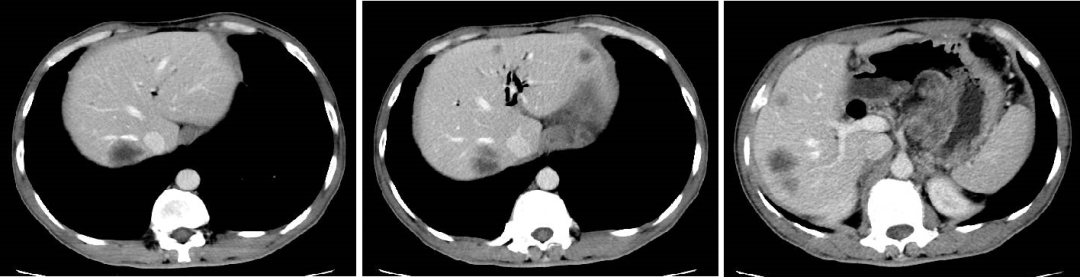

二 病例分享 专家简介 01 基本情况 患者:汪XX,男,63岁。身高 165cm;体重 65kg;体表面积 1.70m2;ECOG 1分。 主诉:反复解黏液血便3天。 对磁共振造影剂过敏,无食物、其他药物过敏史。既往史、个人史、婚育史、家族史均无特殊,无吸烟、饮酒史。 02 初诊病史 现病史:患者2017年3月初无明显诱因下解黏液血便,量中等,为鲜血,反复发作,无恶心、呕血、黑便、腹痛、腹泻、里急后重等不适。遂于2017年3月初就诊我院。 胸、腹、盆腔CT平扫+增强:乙状结肠肠壁明显增厚,肠腔狭窄,增强期强化明显;肝脏多发低密度病灶,增强期不规则强化,考虑乙状结肠癌伴肝脏多发转移。 03 治疗方案 【一线治疗】 2017-06-22 西妥昔单抗+FOLFIRI* Q2W×3 西妥昔单抗 900mg ivgtt D1; 5-氟尿嘧啶 0.6g iv D1,3.5g civ 48h; 亚叶酸钙 0.6g ivgtt D1; 伊立替康 280mg ivgtt D1。 第1疗程结束后黏液血便较前消失,过程顺利,耐受良好,无皮疹、腹泻等不良反应,治疗10疗程,疾病进展。 疗效评估-影像学(部分缓解,PR)。 2017-07-15 乙状结肠癌切除术* 手术记录:肿瘤位于乙状结肠,大小约4cm×3cm,未突破浆膜层,病灶周围可及数个稍肿大淋巴结,未及盆底种植结节。 手术过程顺利,术后恢复良好。 术后病理:(乙状结肠)中分化腺癌,浸润肠壁浆膜下层,两切缘阴性,未见脉管癌栓及神经束侵犯,LN 2/18(+) 2017-08-20 肝转移瘤切除术* 手术记录:肝脏肿瘤位于肝右叶,大小分别约2cm×1.5cm,1cm×1.2cm,其余肝表面未见异常结节,腹腔无腹水、无粘连。 手术过程顺利,术后恢复良好。 术后病理:(肝右叶病灶)中分化腺癌,结合临床病史,符合乙状结肠癌肝转移,肝组织切缘未见癌。 疗效评估-影像学(NED)。 2017-11-06 西妥昔单抗+FOLFIRI* Q2W×3 西妥昔单抗 900mg ivgtt D1; 5-氟尿嘧啶 0.6g iv D1,3.5g civ 48h; 亚叶酸钙 0.6g ivgtt D1; 伊立替康 280mg ivgtt D1; 过程顺利,无皮疹、腹泻等不良反应。每疗程后均予PEG-CSF预防性升白,耐受良好。 疗效评估-影像学(病情进展,PD1)。 胸、腹、盆腔CT平扫+增强:肝左外叶低密度灶,增强期不规则强化,结合病史,考虑结肠癌肝转移,余未见明显异常。 【二线治疗】 2018-03-06 肝左外叶肿瘤切除术* 术中探查见:肿瘤位于肝左外叶,质硬,边界不清,余肝脏表面未见异常结节灶,腹盆腔无腹水。 手术过程顺利,术后恢复良好。 术后病理示:(肝左叶)中分化腺癌,结合临床病史,符合结肠腺癌肝转移。 2018-04至2018-07 卡培他滨+奥沙利铂* Q3W×5 卡培他滨 1.5g BID D1-14; 奥沙利铂 200mg ivgtt D1。 过程顺利、耐受良好,无腹泻、神经毒性等不良反应。 疗效评估-影像学(病情进展,PD2)。 胸、腹、盆腔CT平扫+增强:肝尾状叶结节状异常密度灶,增强期不规则强化,结合病史,考虑结肠癌肝转移,余未见明显异常。 2018-07至2020-04 贝伐珠单抗+卡培他滨* Q3W×21 贝伐珠单抗 500mg ivgtt D1; 卡培他滨 1.5g BID D1-14。 过程顺利、耐受良好,期间曾出现II度腹泻,对症治疗后可恢复正常。无血压升高、出血、蛋白尿、手足皮肤反应。 疗效评估-影像学(最佳疗效,PR)。 疗效评估-影像学(病情进展,PD3)。 腹腔镜肝尾状叶切除术+腹腔粘连松解术* 术中探查见:肿瘤位于肝尾状叶,质硬,边界不清,余肝脏表面未见异常结节灶,腹盆腔无腹水。 手术过程顺利,术后恢复良好。 术后病理示:(肝尾状叶)中分化腺癌,结合临床病史,符合结肠腺癌肝转移。 2020-06至2021-09 贝伐珠单抗+卡培他滨* Q3W×16 贝伐珠单抗 500mg ivgtt D1; 卡培他滨 1.5g BID D1-14。 过程顺利、耐受良好,期间曾出现II度腹泻,对症治疗后可恢复正常。无血压升高、出血、蛋白尿、手足皮肤反应。 疗效评估-影像学(NED)。 疗效评估-影像学(NED)。 【三线治疗】 2021-12-16 西妥昔单抗+TAS-102* Q3-4W×2 西妥昔单抗 900mg ivgtt D1; TAS-102 60mg BID D1-5,8-12。 过程顺利、耐受稍差,期间出现II度骨髓抑制(三系减少),对症治疗后可恢复正常。无皮疹、输液反应等。 疗效评估-影像学(部分缓解,PR)。 04 治疗小结